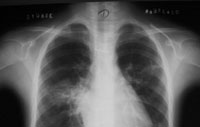

X线胸片1: 入院时(病程2个月时)胸片(右肺门外及左下肺心缘旁可见片影,左上肺纹理乱,右肺门著明,心影丰满) X线胸片

2:入院第7天(病程67天)胸片:右肺门增浓,边缘模糊,下肺纹理模糊,左肺纹理粗乱,下肺纹理模糊

任甄华 主治医师(放射科):X线胸片对于提示肺栓塞有重要参考价值,单纯肺栓塞胸片可能有五种表现:(1)缺血性改变:局部血管纹理减少,即Westermark征;(2)肺血管大小的改变;(3)心脏变化;(4)肺体积缩小;(5)胸膜渗出。值得强调的是,感染性心内膜炎引起的肺栓塞影像学改变与其他病因引起者不同,典型表现为散在、双侧的外周结节与不同程度的肺空洞性损害,损害呈圆形或楔形,多发生在下肺的外侧部分。本病例就体现了这一特点(见附图),这可能与栓子较小且携带病原菌,造成栓塞部位的继发感染有关。

但必须指出,肺栓塞的X线胸片表现多种多样,呈典型锥形改变的非常少见,部分肺栓塞的胸片可看不见任何异常表现。相当一部分胸片呈肺浸润表现,与肺炎相似。可从以下两点加以区别:①肺部一侧病变吸收,而另一侧出现新阴影的多发病变;②片影吸收呈“溶化征”,而肺炎吸收中片影出现密度不均现象,由此可见,在诊断中胸片的动态观察更为重要。有以上表现者应高度怀疑肺栓塞,再结合患儿是否存在高危因素,临床可做出正确诊断。切勿仅凭胸片轻易排除肺栓塞。本例患儿存在感染性心内膜炎、三尖瓣赘生物的基础病变,2个月病程中肺部阴影变化了3次,每次均为原有病灶吸收,在不同部位又出现了新的浸润影,结合临床表现,肺栓塞可确诊。